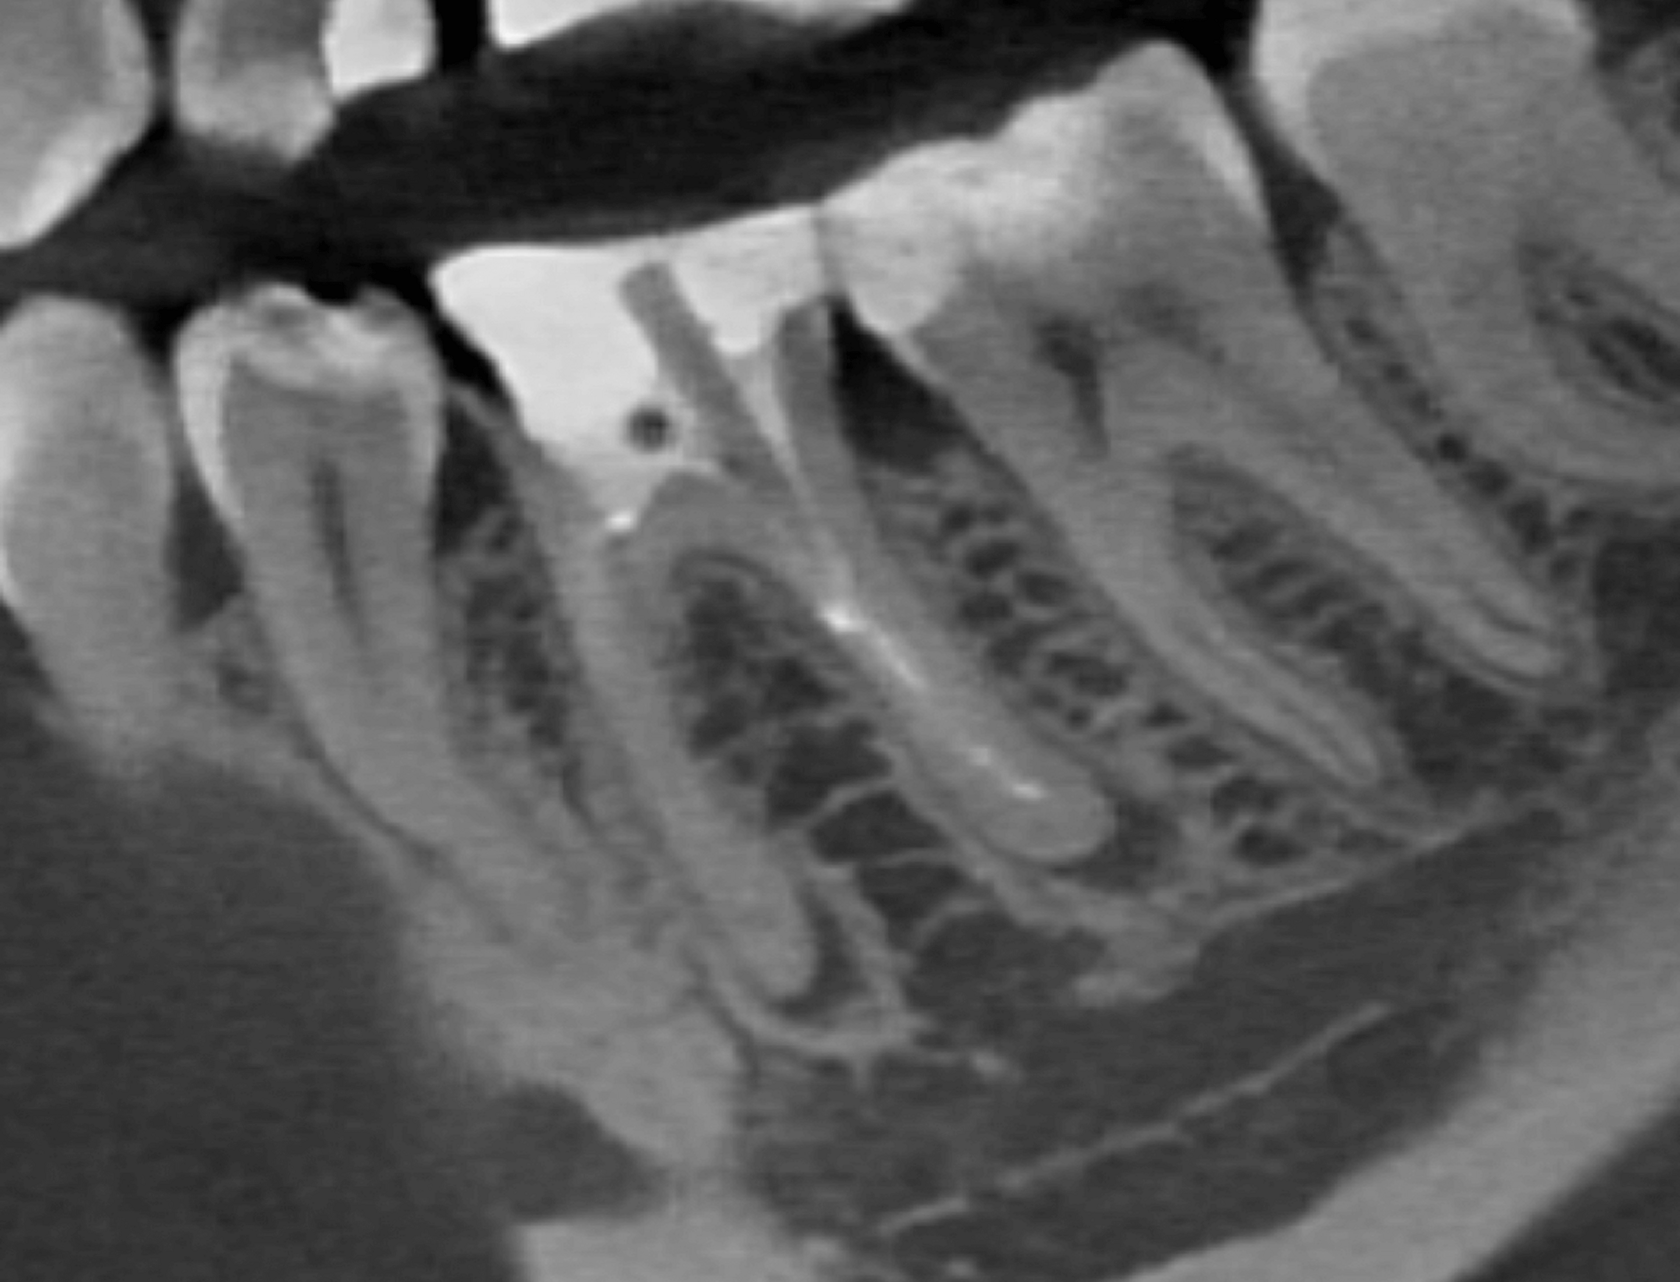

1. The patient presented with tooth #46 (lower right first molar) diagnosed with apical periodontitis, featuring two fractured endodontic instruments in the mesial root canals alongside overprepared canal orifices. Additionally, the distal root contained two misaligned fiber posts that had been cemented non-axially within the canal space, further complicating the endodontic retreatment. (Image 1,2,3)